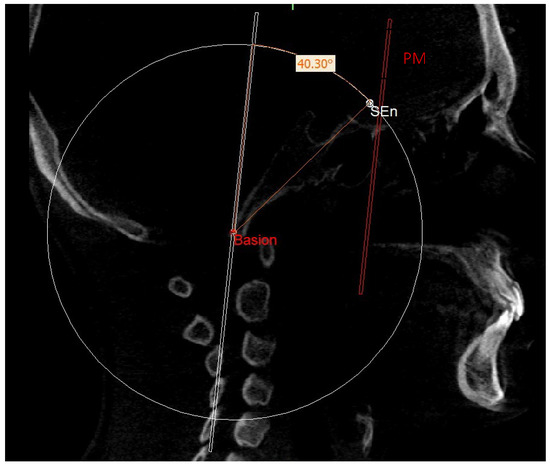

| SEn | SE neutral: the point of a circumference with the center in Ar and the radius equal to the MCF, in which an angle of the skull base equal to 40.3° is obtained |

| PMn | PM neutral: the line parallel to the PM forming at the point SEn an ideal angle of 40.3° with the MCFn |

| MCFn | MCF neutral, Ar—Sen |

| SE neutral (SEn) | / | Point of a circumference with center in Ba and radius equal to MCFx, in which an angle of the skull base equal to 40.3° is obtained | / |

| Right SE neutral (rSEn) | / | Point taken arbitrarily on the right side of the SEn on the same arc of circumference | / |

| Left SE neutral (lSEn) | / | Point taken arbitrarily on the left side of the SEn on the same arc of circumference | / |

| MCF neutral (MCFn) | Plane passing through the Ba, rSEn and lSEn which forms an angle of 40.3° with the PMn at the SEn point |

| PM neutral (PMn) | Plane parallel to the PM such as to form an ideal angle of 40.3° with the MCFn at the SEn point |